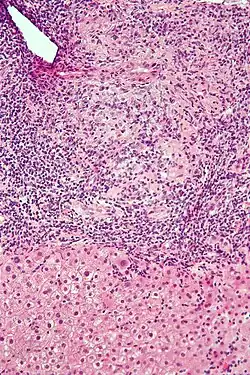

Low-magnification micrograph of PBC, H&E stain -

On microscopic examination of liver biopsy specimens, PBC is characterized by chronic, nonsuppurative inflammation, which surrounds and destroys interlobular and septal bile ducts. These histopathologic findings in primary biliary cholangitis include:[32]

- Inflammation of the bile ducts, characterized by intraepithelial lymphocytes

- Periductal epithelioid granulomas.

- Proliferation of bile ductules

- Fibrosis (scarring)